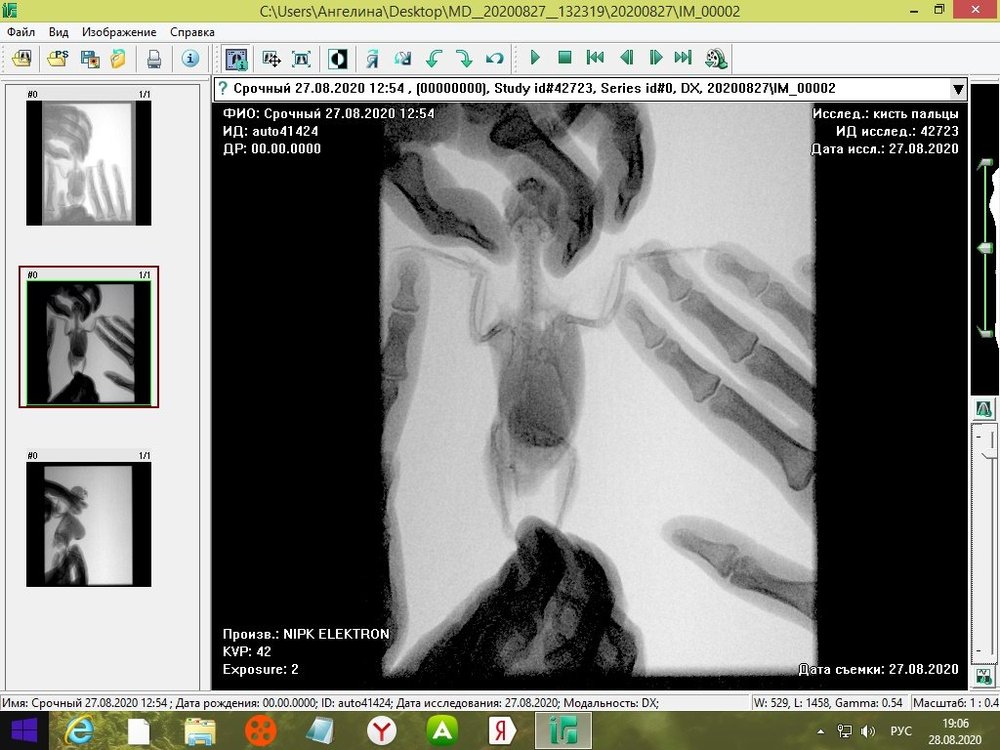

tanushka-sol2020 Опубликовано 27 августа, 2020 Автор #15 Опубликовано 27 августа, 2020 Некадрированные исходные снимки --- щёлкните полосу ниже. Скрытый текст

Кузяныч Опубликовано 28 августа, 2020 #16 Опубликовано 28 августа, 2020 Ох, бедная волнушка... В помёте на шли бактерии (++), слизь (+), жир (+), клетчатку (++)... Есть и непонятные для меня записи... По рентгену на втором снимке справа мне видится что эта огромная припухлость --- растянутый зоб... 18.08.2020 в 17:16, tanushka-sol2020 сказал: Что за опухоль? Она в моих руках меняется: то сморщится, то раздувается как шар надувной... Неужели, действительно зоб?... @tanushka-sol2020, срочно звоните Зосе, просите посмотреть снимки. Мазок из клюва... уф-ф... не знаю пока на сколько он нужен... Если на нистатине птице легче, то давайте его --- придерживайтесь дозировок, что давала вам Зося. Расположите лесенку горизонтально чтоб попугайчик экономил силы. Установите всё как можно ниже к полу. Проверьте, чтоб птичка не пыталась лезть выше и не висла на стенке. Помёт оранжевый... возможно, действительно, печень страдает... Карсил не отменяйте... За гепатовет и как вообще быть я не могу сказать. Нужно чтоб Зося посмотрела рентген. Свяжитесь, пожалуйста, с ней. У меня такое впечатление, что у этой волнушки растянут зоб и от этого плохо уходит и застаивается, протухая, пища.

tanushka-sol2020 Опубликовано 28 августа, 2020 Автор #17 Опубликовано 28 августа, 2020 (изменено) @Кузяныч К сожалению, от нистатина у нее сильно страдает печень. Я не стала ей давать, почти 3 недели принимали. Но срыгивание снова вернулось. Когда я собирала мазок из глотки, она потом срыгнула на одежду. Капли были песочного цвета и консистенция, как каша жиденькая. Но с запахом. Переживаю, вдруг неправильно сделала мазок, впервые же. Во вторнике будет готов анализ. Отпишусь. Рентген делали в больнице, я их кое-как уговорила. Первый "блин с комом", тоже выложила. Вдруг качества нет на снимке, что показал. Завтра Зосе позвоню. Спасибо, что ответили. Эти снимки неудачные выше, племянница скидывала. Я немного контраст отрегулировала, чтобы было видно. Изменено 28 августа, 2020 пользователем tanushka-sol2020